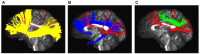

The existence of the superior fronto-occipital fasciculus (SFOF) in the human brain remains controversial. The aim of the present study was to clarify the existence, course, and terminations of the SFOF. High angular diffusion spectrum imaging (DSI) analysis was performed on six healthy adults and on a template of 842 subjects from the Human Connectome Project. To verify tractography results, we performed fiber microdissections of four post-mortem human brains. Based on DSI tractography, we reconstructed the SFOF in the subjects and the template from the Human Connectome Project that originated from the rostral and medial parts of the superior and middle frontal gyri. By tractography, we found that the fibers formed a compact fascicle at the level of the anterior horn of the lateral ventricle coursing above the head of caudate nucleus, medial to the corona radiate and under the corpus callosum (CC), and terminated at the parietal region via the lower part of the caudate nucleus. We consider that this fiber bundle observed by tractography is the SFOF, although it terminates mainly at the parietal region, rather than occipital lobe. By contrast, we were unable to identify a fiber bundle corresponding to the SFOF in our fiber dissection study. Although we did not provide definite evidence of the SFOF in the human brain, these findings may be useful for future studies in this field.